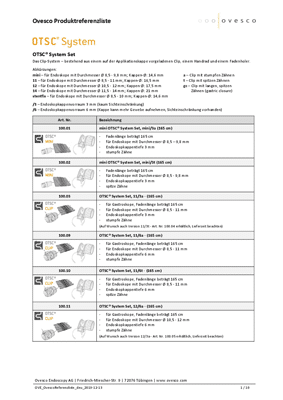

Das BARS® Set

Das BARS® wird als Prozedur-Set geliefert und besteht aus den folgenden Produkten

- BARS® Applikationskappe mit montiertem Clip und Faden

- Zwei zusätzliche Arbeitskanäle, die in die Kappe integriert sind

- BARS® Anchor (1x Silver & 1x Black)

- BARS® Handrad

- Insertion balloon

- Führungsdraht

- Fadenholer

- Space keeper balloon

Maße und Spezifikationen

| Kappenlänge | 35,3 mm |

| Clipbreite = Kompressionsbreite [a] | 12,4 mm |

| Min. Außendurchmesser [b] | 19,5 mm |

| Max. Außendurchmesser [c] | 21,2 mm |

| Innendurchmesser Kappe [d] | 13,1 mm |

| Kompatibel Endoskopdurchmesser [e] | 10,0–12,0 mm |

| Innerer BARS Arbeitskanal [A] | 3,0 mm Arbeitskanaldurchmesser | Max. 2,8 mm Instrumentendurchmesser |

| Endoskop-Arbeitskanal [B] | min. 3,7 mm |

| Äußerer BARS Arbeitskanal [C] | 2,8 mm Arbeitskanaldurchmesser | 2,6 mm Instrumentendurchmesser |

| Führungsdraht | 3700 mm Länge | 0,76 mm (0,03‘‘) Durchmesser |